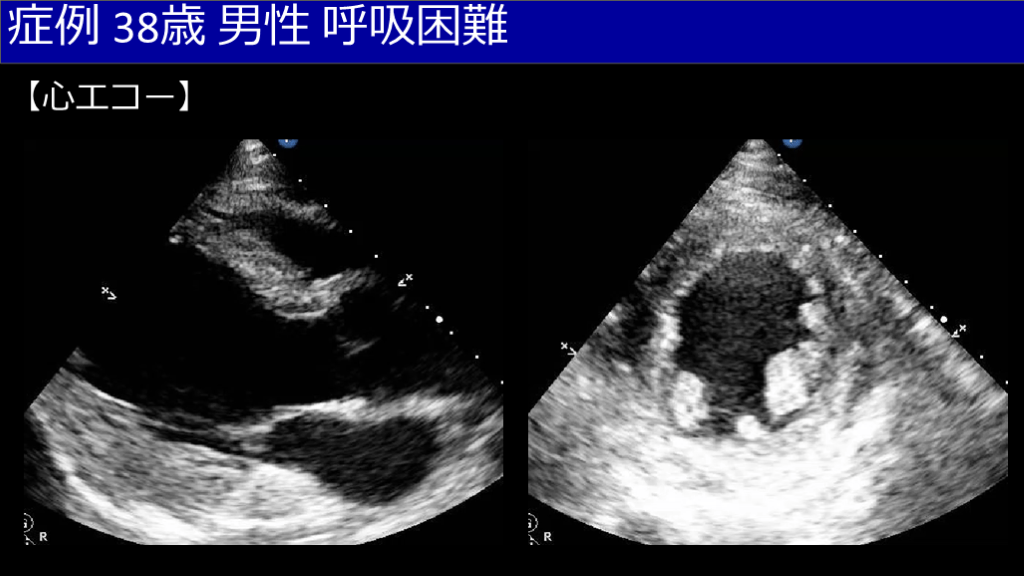

症例 38歳 男性 呼吸困難 【心エコー】